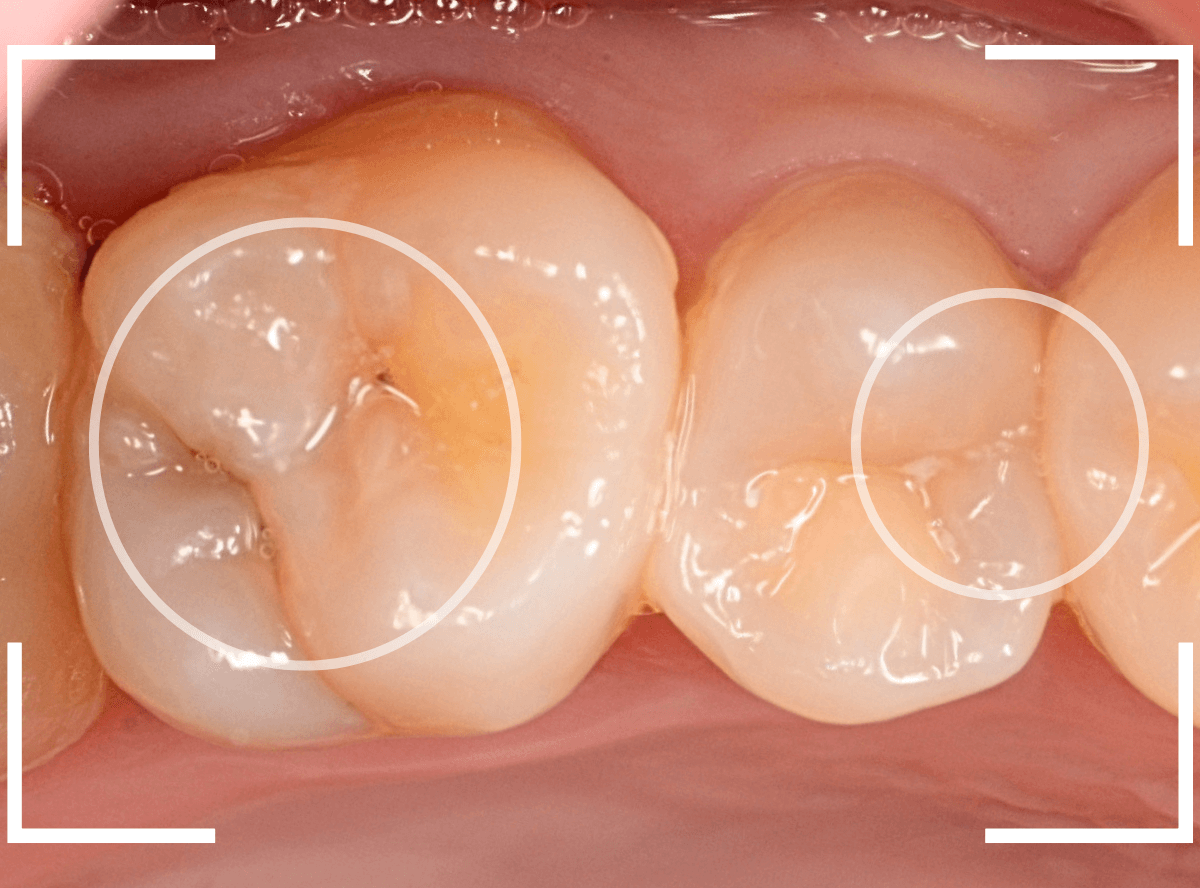

Case.25 深い虫歯の治療~無事にセラミック・インレーへ

今回は、上の奥歯が深くて広い虫歯になっていた方のケースです。

〇部が虫歯の部分です。

この写真からは深い虫歯があるのは想像つきません。

レントゲン写真で確認します。